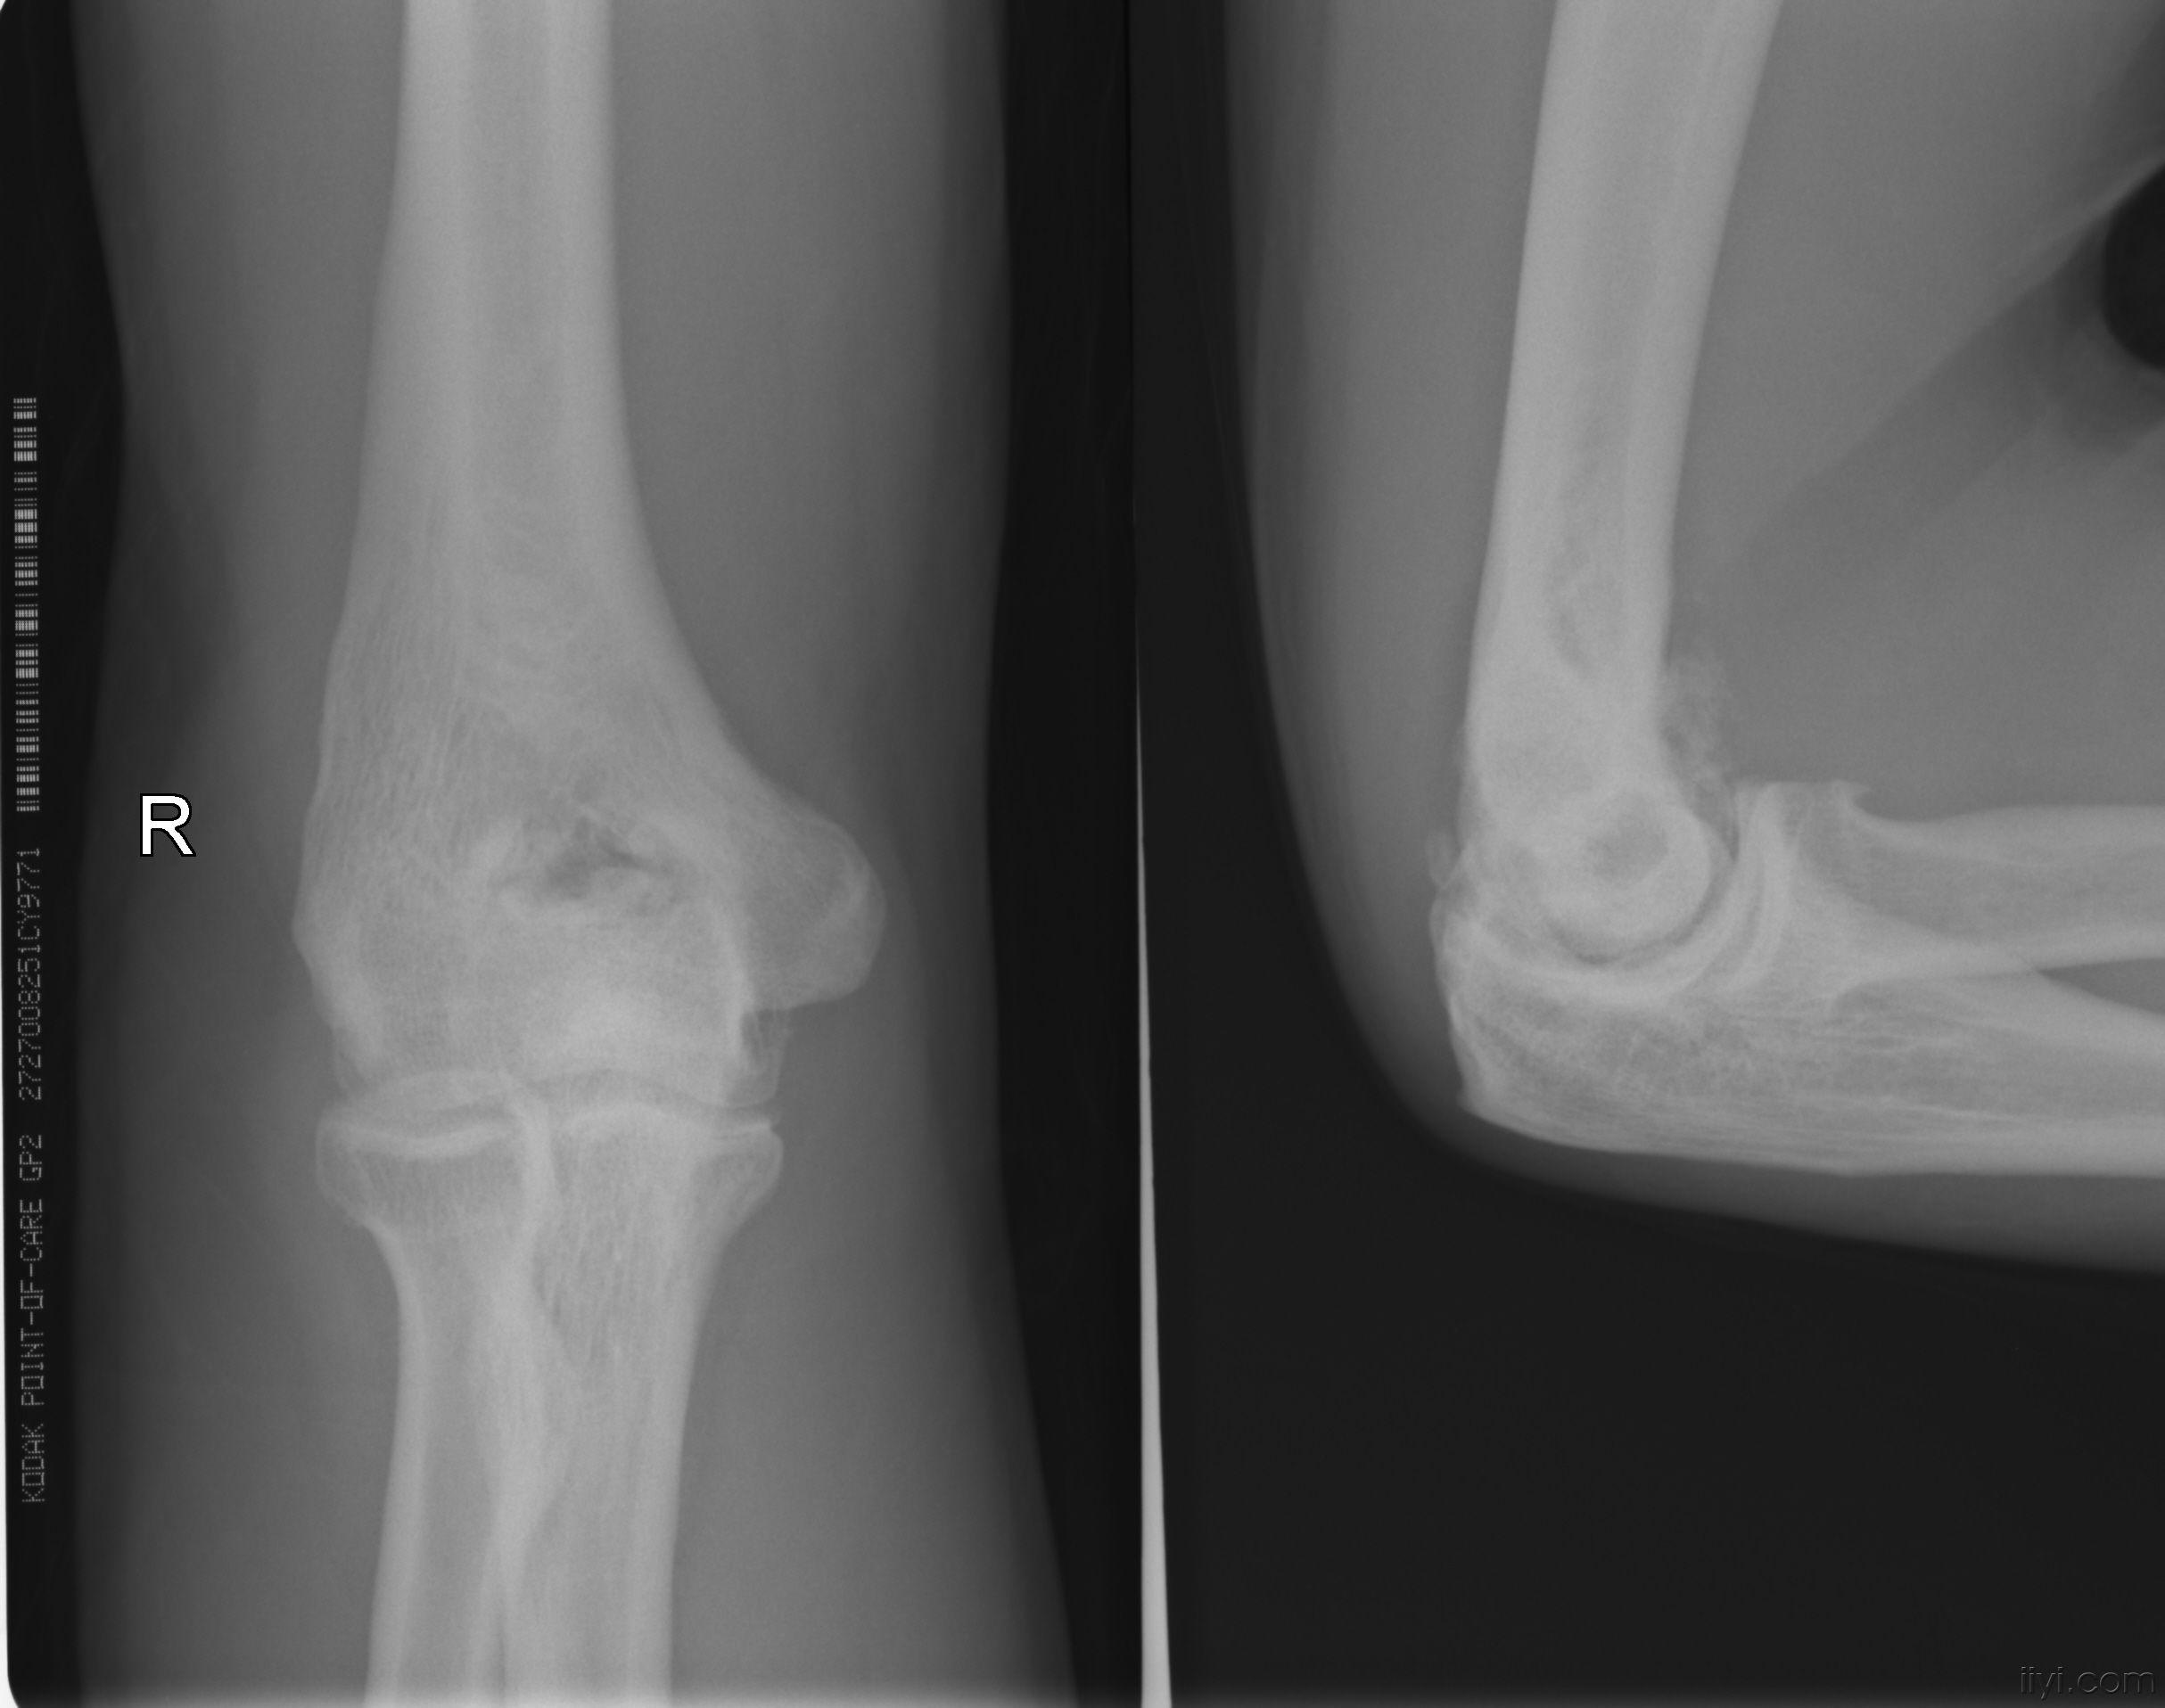

胳膊肘的正常片子图

胳膊肘的正常片子图,正常右胳膊拍片子图片

一张肘关节的片子

22不慎摔伤,右肘部着地,进行右肘关节正侧位x线片,结果诊断为"右肱骨